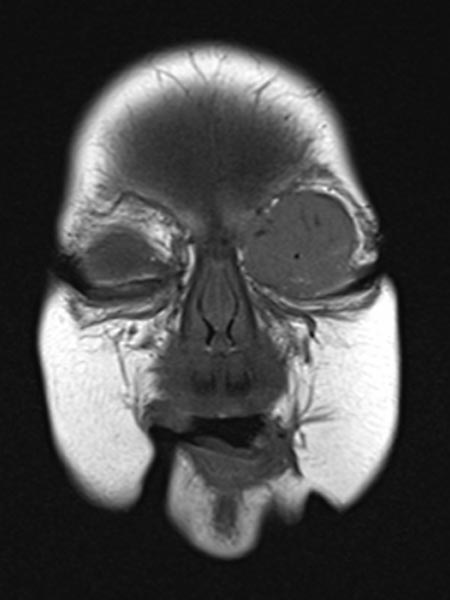

Die koronare, native T1-gewichtete MRT zeigt die Raumforderung homogen hypointens. Zentral einige wenige kleine flow-voids durch stark perfundierte arterielle Gefäße.

T1-gewichtete, koronare MRT nach Kontrastmittelgabe zeigt einen homogen stark Kontrastmittel aufnehmenden, soliden, scharf angegrenzten Tumor am linken Auge. Dies ist klar hinweisend auf ein infantiles Hämangiom als vaskulärer Tumor.

Die T1-gewichtete, koronare MRT nach Kontrastmittelgabe etwas weiter dorsal zeigt die Ausdehnung der KM-aufnehmenden soliden Raumforderung bis weit in die mediale Orbita des linken Auges mit Verlagerung des Bulbus nach kaudal und lateral.